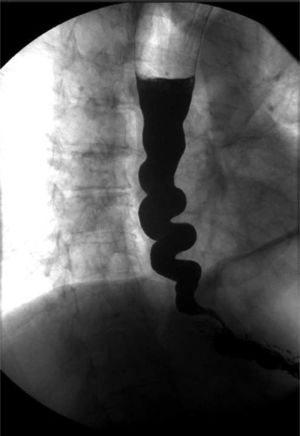

A 75-year-old man was referred due to dysphagia with each meal, weight loss of 5 kg and non-acidic regurgitation over the past 20 years (Eckardt score of 7/12). On upper gastrointestinal endoscopy, the oesophagus showed a striking spiral morphology with gastro-oesophageal junction spasticity (Fig. 1). An oesophagogram revealed a “corkscrew” image (Fig. 2). High-resolution manometry (HRM) showed elevated mean integrated relaxation pressure (46 mmHg; normal <15) and aperistalsis with pan-pressurisation every time the patient swallowed, consistent with type 2 achalasia (Fig. 3).1 Peroral endoscopic myotomy (POEM) was performed, revealing posterior myotomy measuring 12 cm in the oesophageal branch and 2 cm in the gastric branch, in 120 min, with no adverse events, although the procedure was technically complex due to the tortuosity and spasticity of the patient's oesophagus. Three months later, the patient showed significant improvement of both his signs and symptoms (Eckardt score of 1/12) and his oesophagogram and HRM findings.

Corkscrew oesophagus is a radiological term that alludes to the shape of the barium column in the distal oesophagus, classically associated with distal oesophageal spasm and, rarely, with achalasia.2 POEM is a treatment option that requires suitable prior planning given the morphological and functional characteristics of the oesophagus.